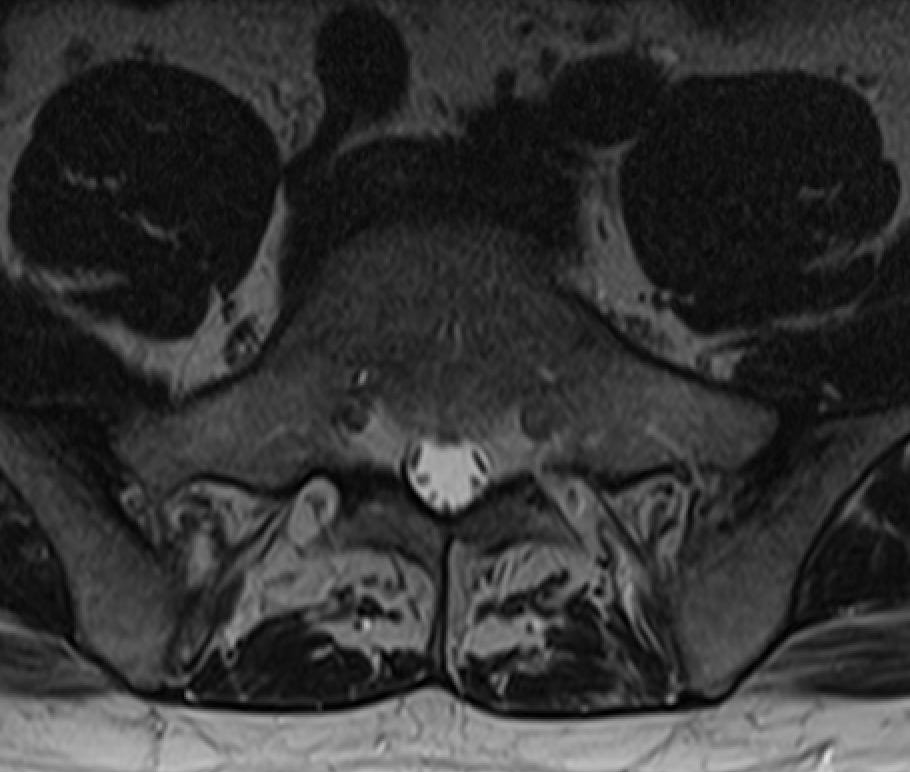

What do you see?

This is from my MRI. Lovely, isn’t it?